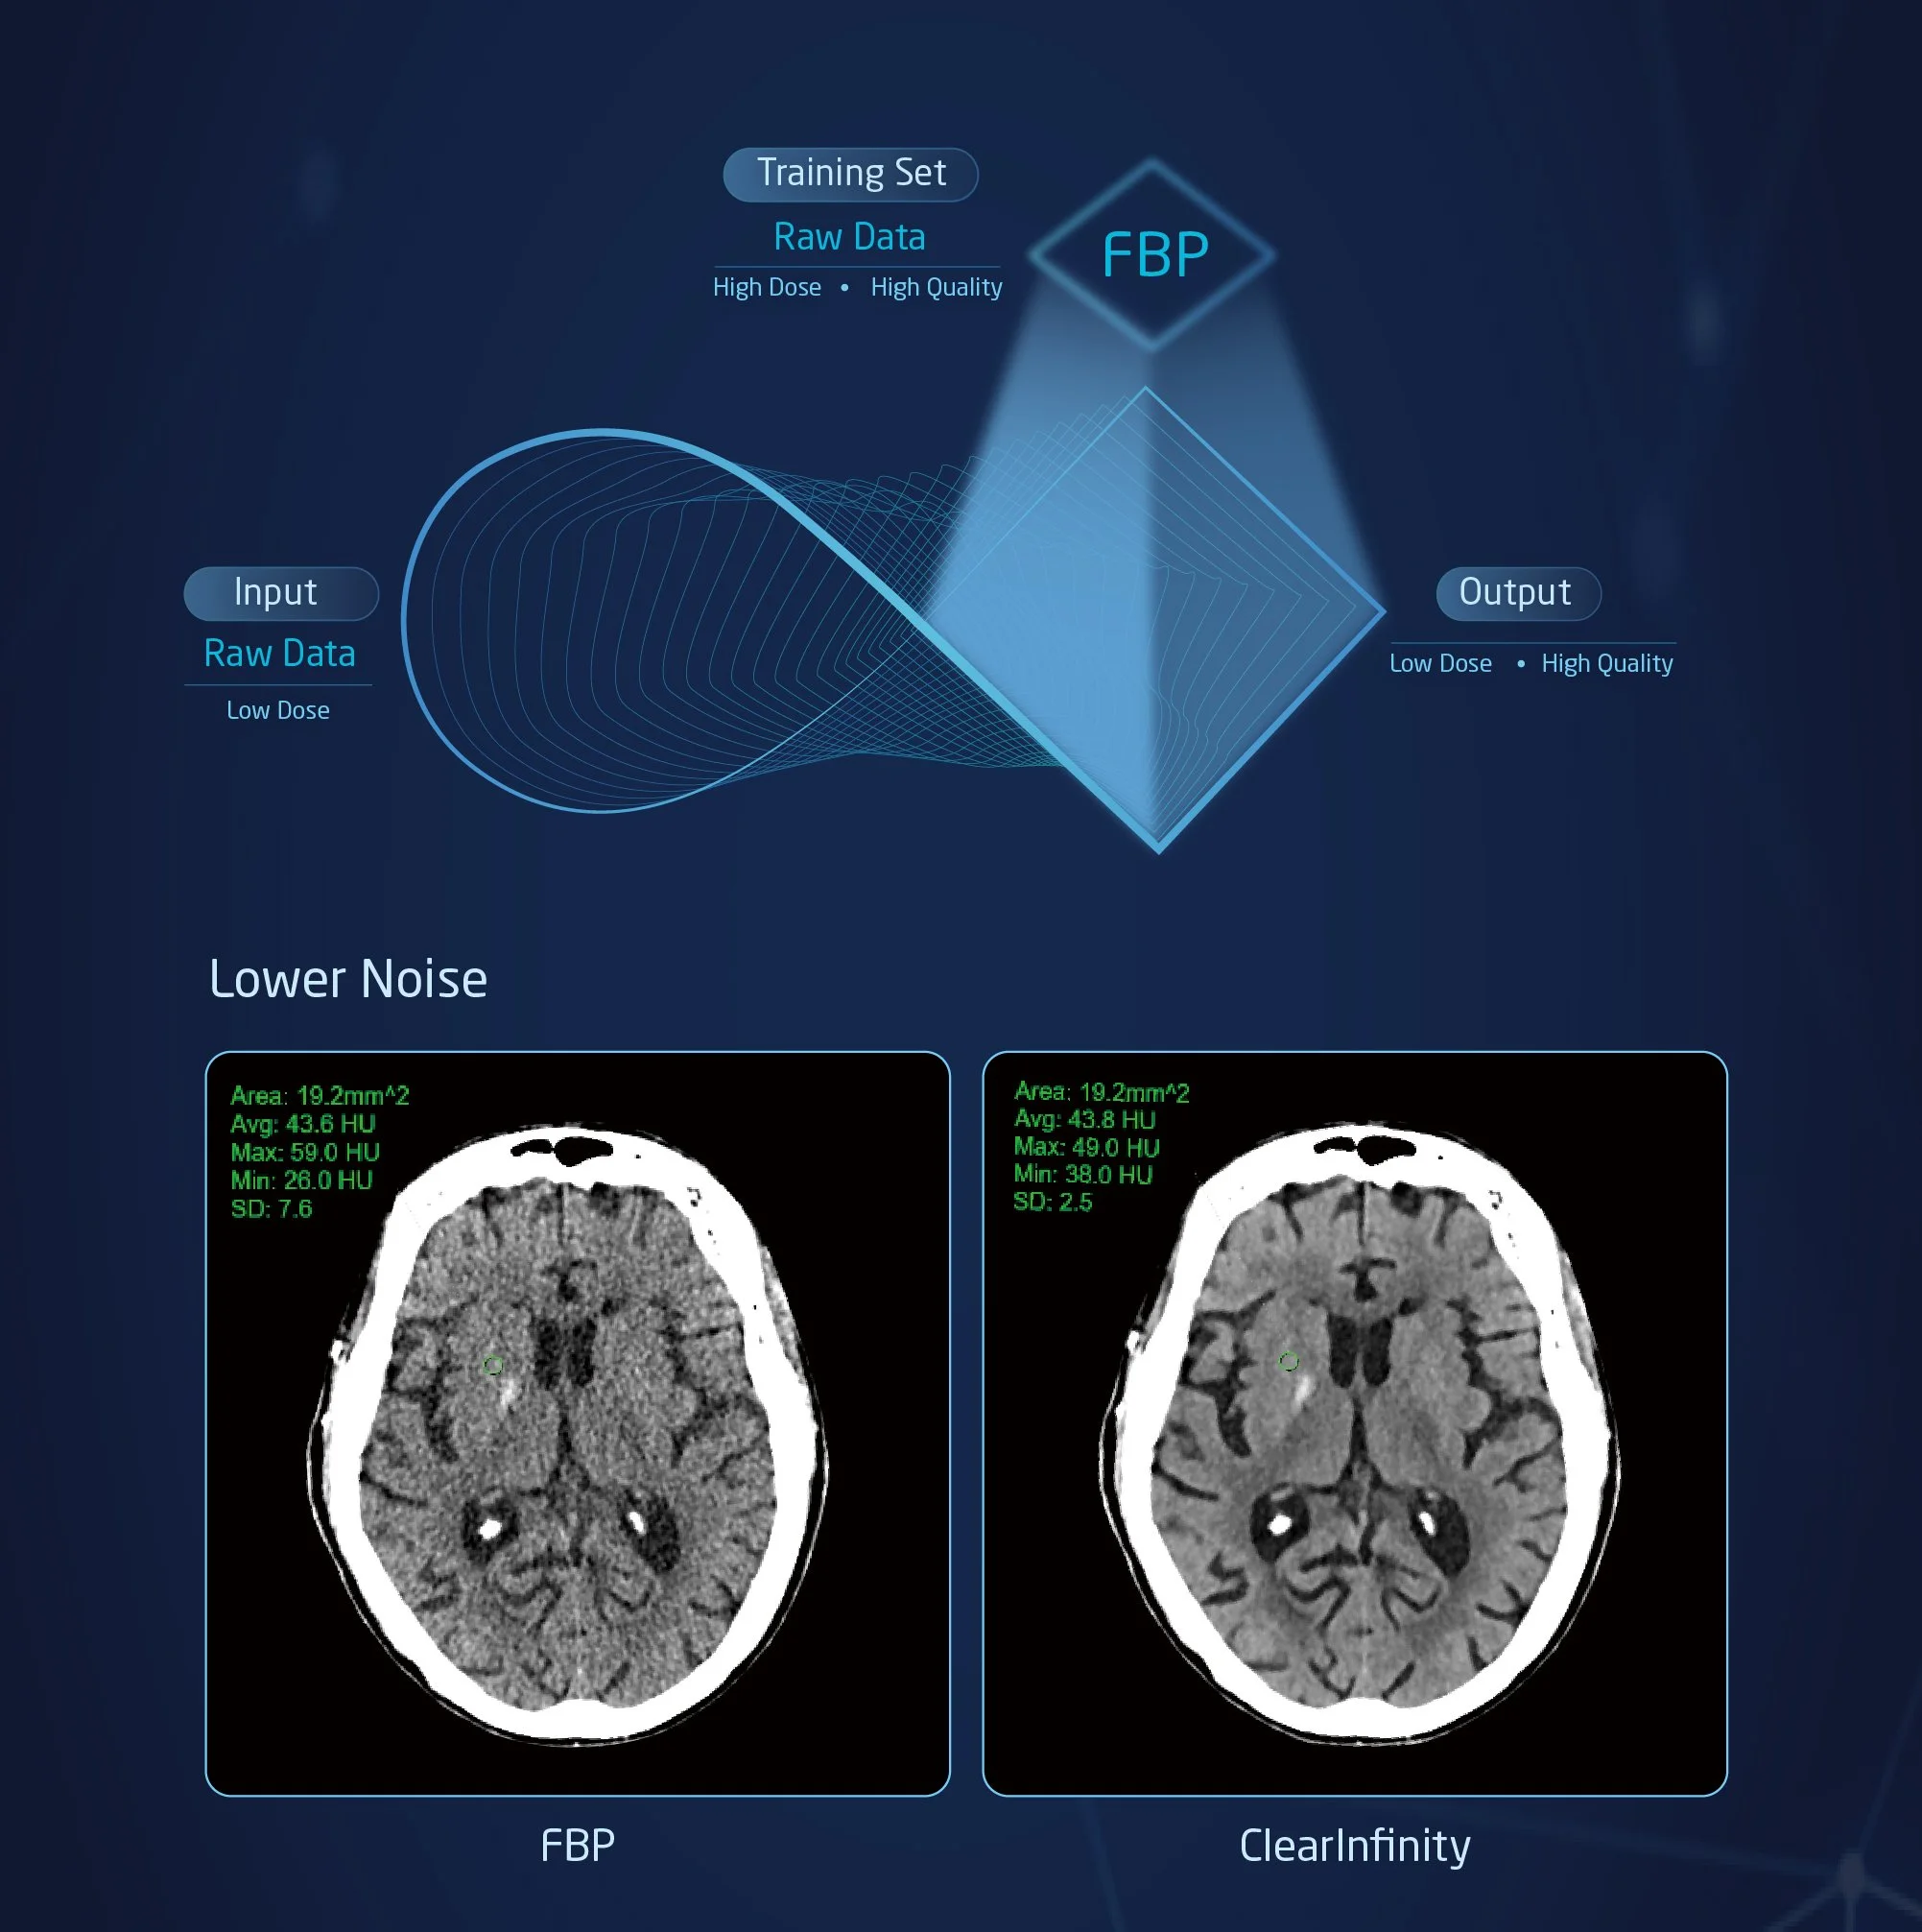

As a standard option with the NeuViz 128, ClearInfinity AI allows for lower doses to patients without compromising image quality. ClearInfinity AI is a deep learning reconstruction algorithm trained to lower noise and artifacts wile creating better image texture and detectability.

Advanced detector design: Detector Micro-STAR. Deep learning reconstruction algorithm with ClearInfinity.

ClearInfinity AI